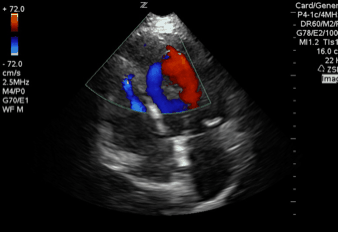

QA of the Day: great apical 4 chamber demonstrating mitral then flow through a VSD #pocus #foamed #foamus